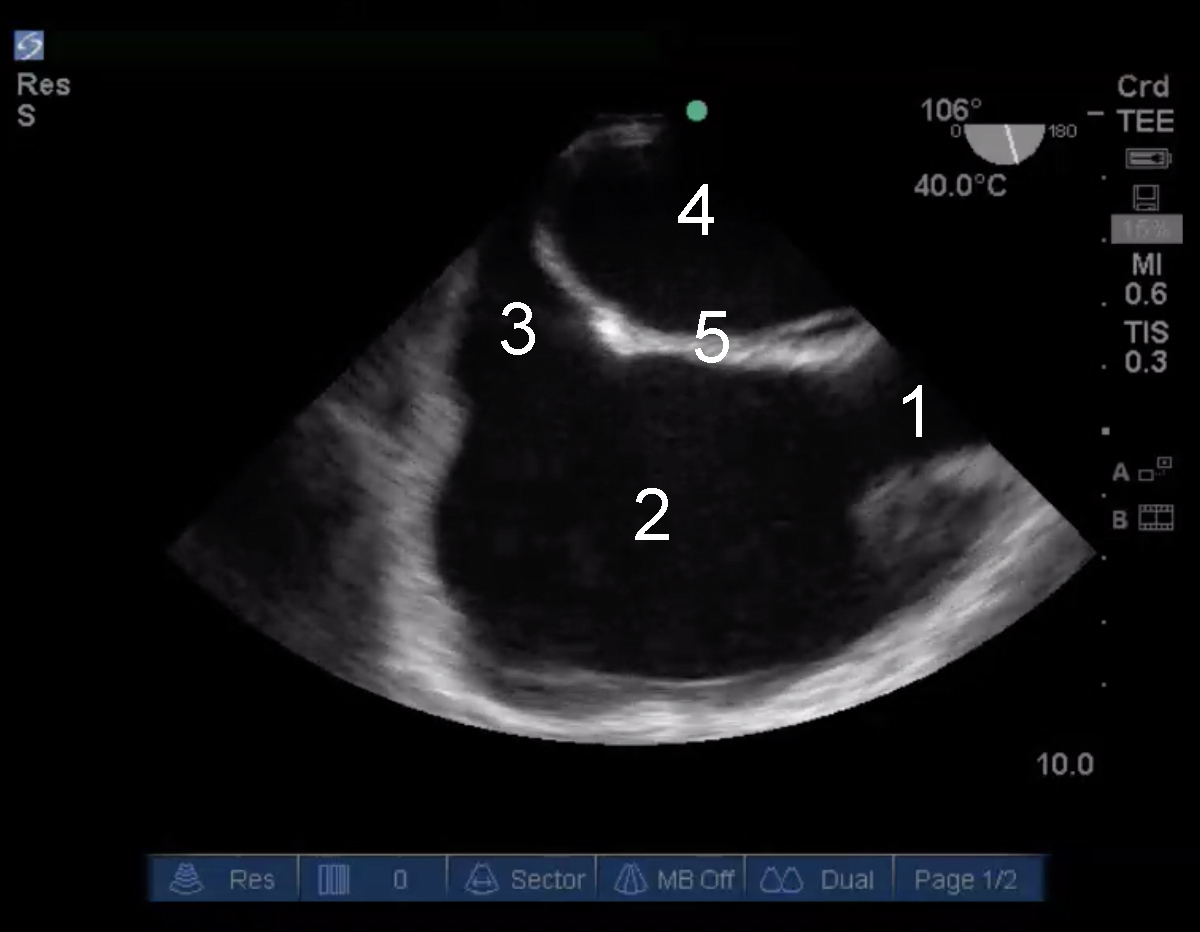

Cardiac 2 TEE Mid Esophageal Bicaval SVC Image

1. Superior Vena Cava (SVC)

2. Right Atrium (RA)

3. Inferior Vena Cava (IVC)

4. Left Atrium (LA)

5. Interatrial Septum